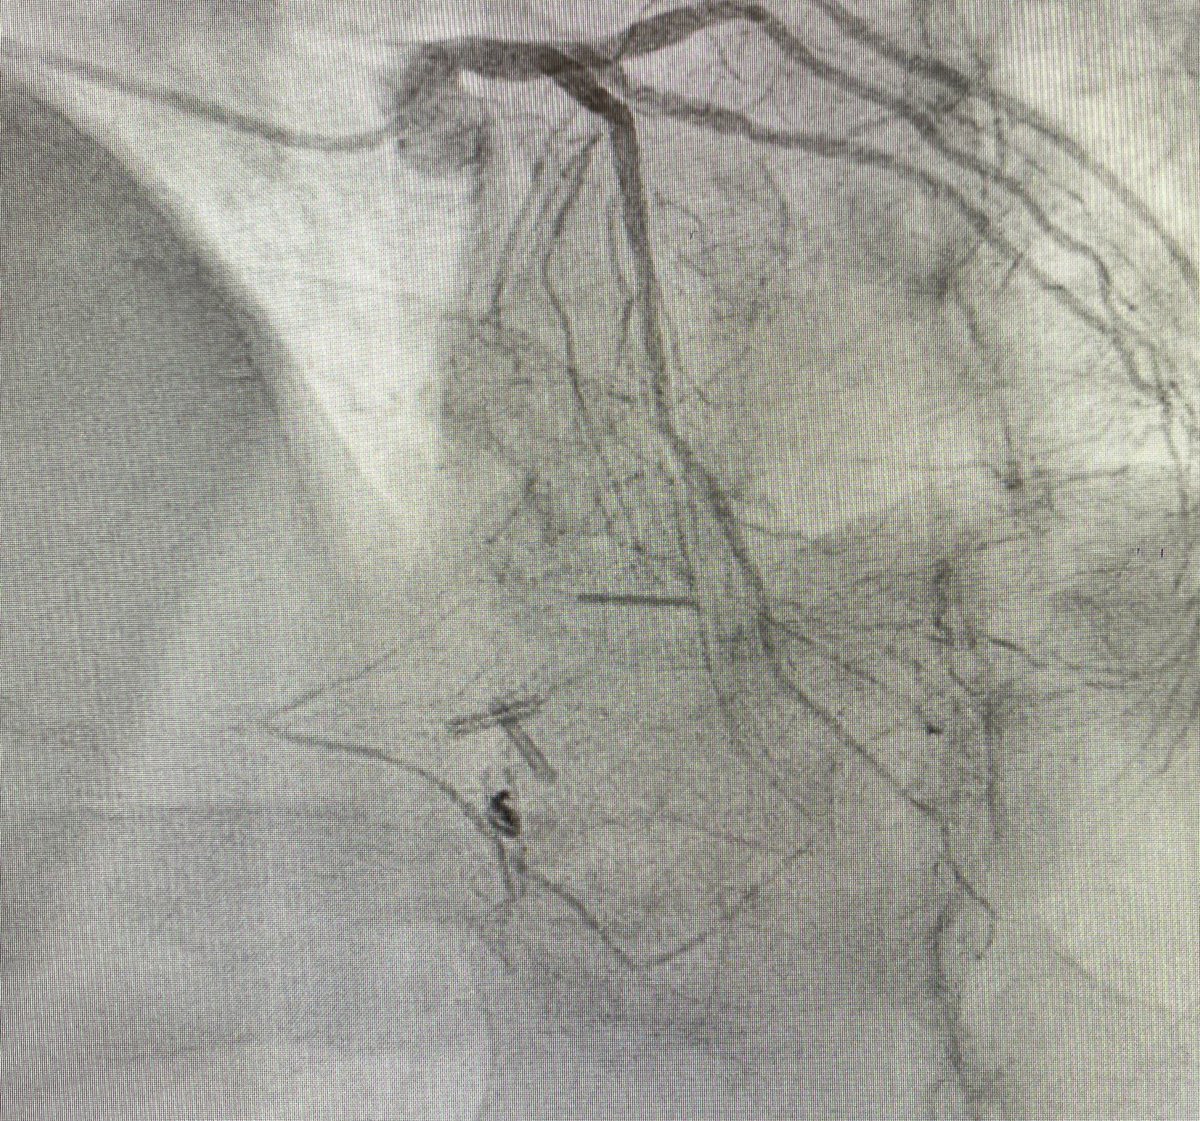

.@DrNjambi of @MGHHeartHealth received @SCAI-WIN's Complex and High-Risk Interventional Procedures (CHIP) award. The award enables #cardiology fellows or practicing cardiologists to pursue an additional year of advanced training on work in the cardiac catheterization lab. (1/2)